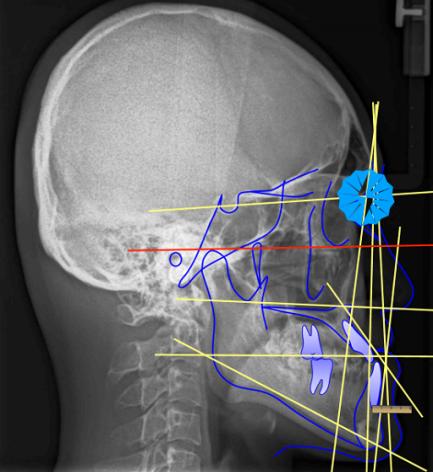

做过牙齿矫正的朋友都知道,做矫正前检查正畸医生一定会让你拍一张头影侧位片。从技术层面看,医生会根据你的X片做投影测量具体来分析。

我常用的方法, 从鼻根点N做眶耳平面的垂线, 是测量上下颌骨前后位置的基准线。A点到垂线的距离和Pg颏前点到垂线的距离分别代表着上颌骨的位置和下颌骨的位置。 标准值通常是成人上颌:1毫米, 下颌通常是:-2~-4毫米。 如果是儿童,下颌的标准值可能是:-6~-8mm, 上颌A点位于该垂线上(0mm);超出这个标准值,就会判断是骨性问题。(如图1)

图1